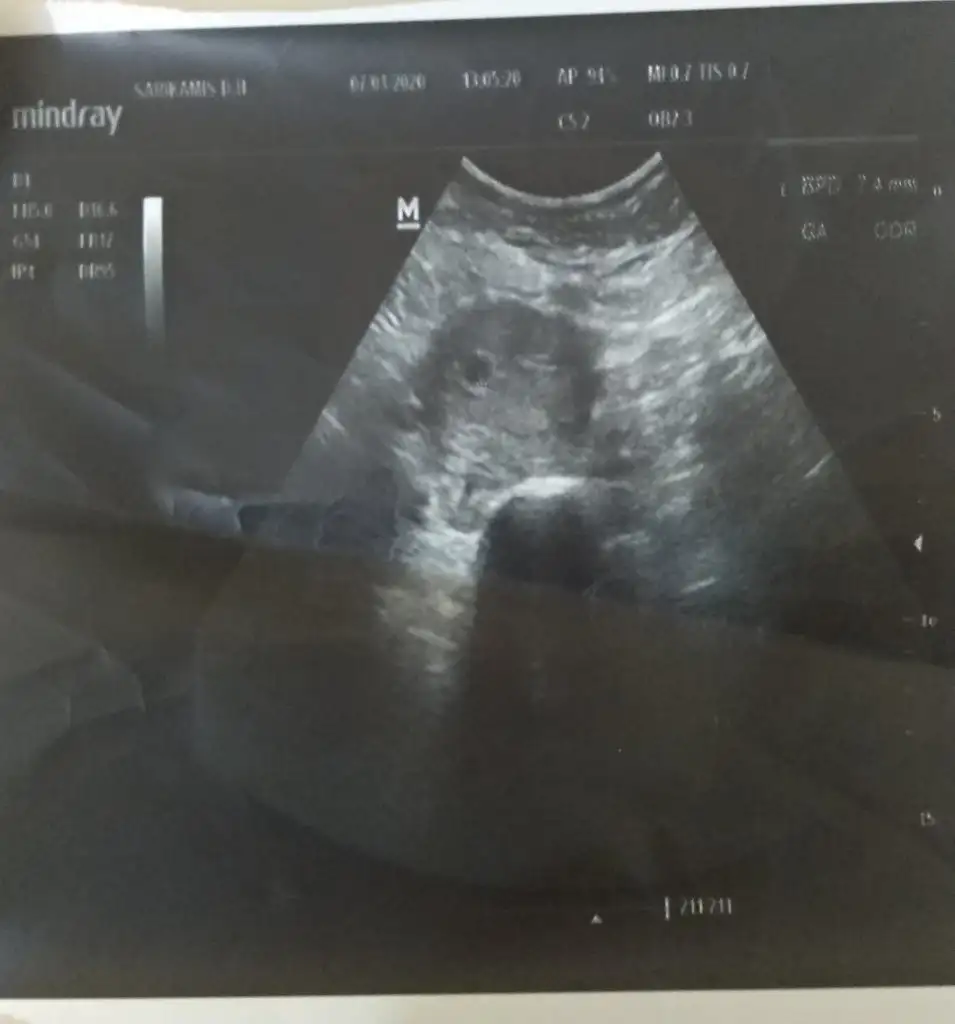

Kızlar kese dün bu kadardi bugün görüntü bile vermedi daha küçük dimi ya o üste c ile başlayan da kesenin boyutu 5+2 ile mı uyumlu demek çünkü o zaman benim hesabım 5+6 ydi acaba geriden geldiği için bebek görünmemiş olabilir mi?